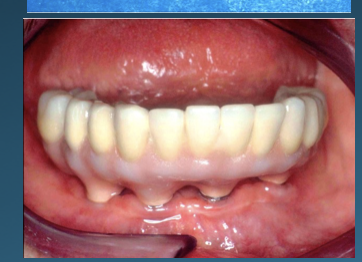

(42.) Fixed-removable prosthesis.

Figure 42

(43.) Fixed-removable prosthesis.

Figure 43

(44.) Fixed-removable prosthesis.

Figure 44

(45.) Fixed-removable prosthesis.

Figure 45

At the initial patient examination, several factors in addition to restoration shape should be considered when planning implant-supported restorations. History of periodontal disease, irregular maintenance visits, clinical appearance of the remaining teeth and soft tissue conditions may indicate increased risk of peri-implantitis. Patient dexterity, adaptability, willingness, and capability to carry out intended home care should be considered. Patient's mental conditions including dementia may influence the design of this as well as unrealistic patient expectations. A "High water original Branemark design" or no treatment may be indicated. Especially when implant location makes access, a fixed-removable design may be necessary to reduce risk of peri-implantitis may be indicated (Figures 42 through Figure 45). Considering that oral biofilm accumulation, even at two weeks post prosthetic insertion is documented, periodic removal of screw retained restorations is less effective than daily access to disrupt bacterial plaque accumulation.